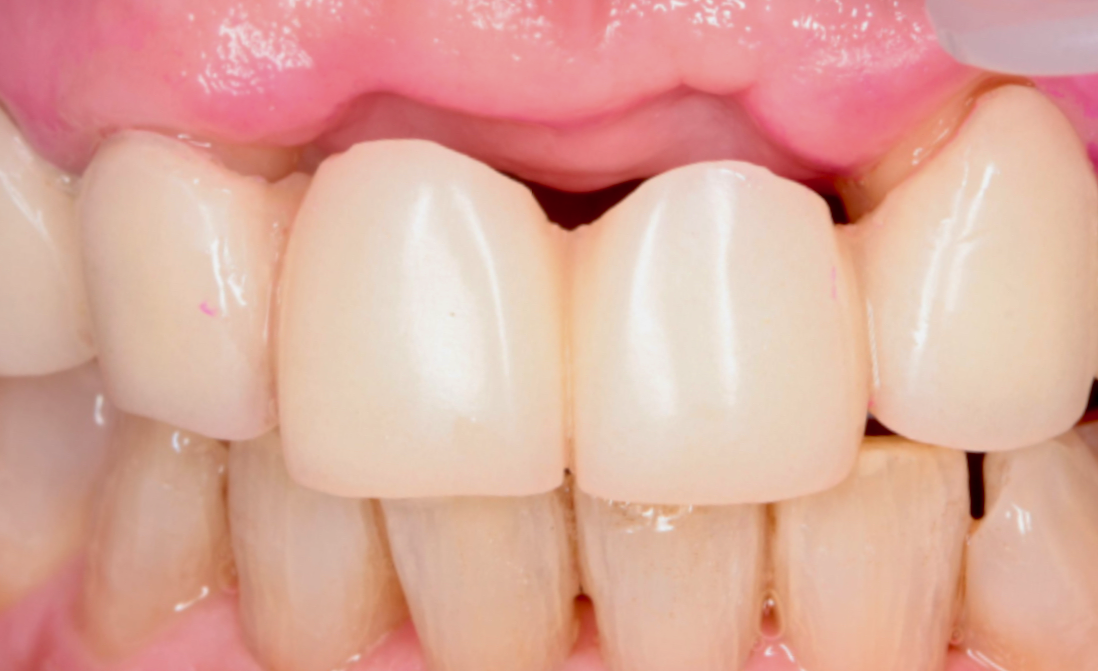

型取り時

抜歯した部分の歯ぐきの形がある程度安定したため、最終的なブリッジを作製するための型取りを行いました。

ブリッジでは、見た目だけでなく、清掃しやすい形にすることも大切です。 -

装着時

慎重にセットし、しっかりと噛み合わせ調整を行なった。

骨の吸収が大きかったため、通常よりも歯の長さがやや長くなる可能性があった。

ただし、笑った時に歯ぐきが大きく見えるタイプではなかったため、患者様と相談のうえ、見た目にも大きな違和感が出にくい設計でブリッジを作製した。 -